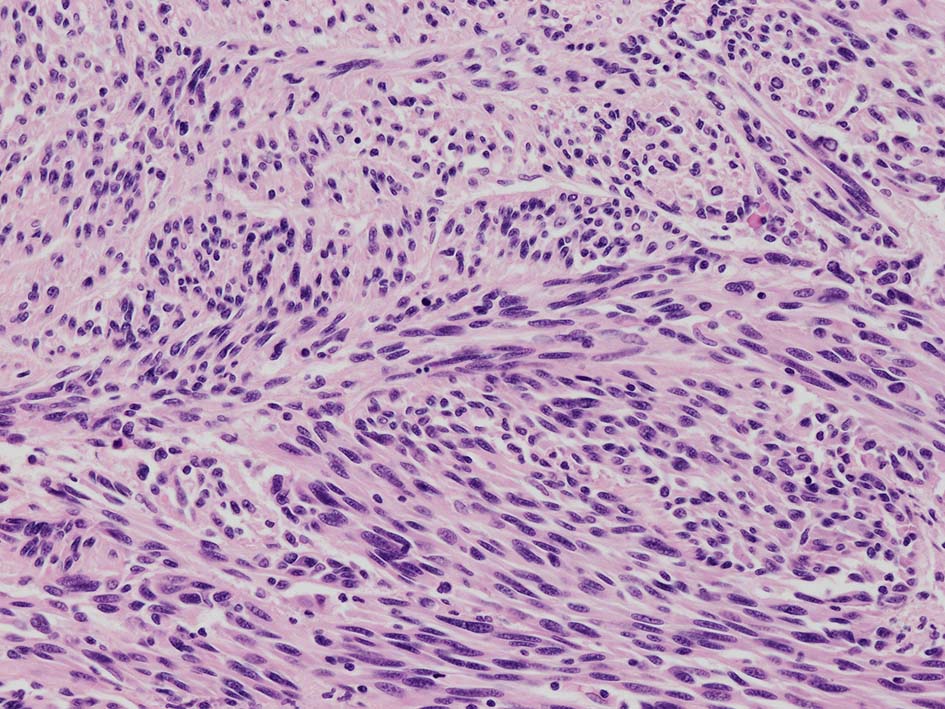

紡錘形異型メラノサイトが著明な間質反応(desmoplasia)を伴い増殖する特殊な色素性病変。*1. desmoplastic neurotropic melanomaは, desmoplastic melanomaのうち神経向性(neurotropism:神経周囲侵襲像)がめだつものでReedら*2が最初に報告した。

いずれも腫瘍細胞の異型性が乏しく, 背景の間質反応がめだつこと, メラニンの存在が目立たないことが特徴である。

“このため両者を臨床的にも病理学的にも色素性病変と診断することが困難”であり, 初回生検時には瘢痕病変や皮膚線維腫などと誤認されることが多い。

再発腫瘤病変の組織像